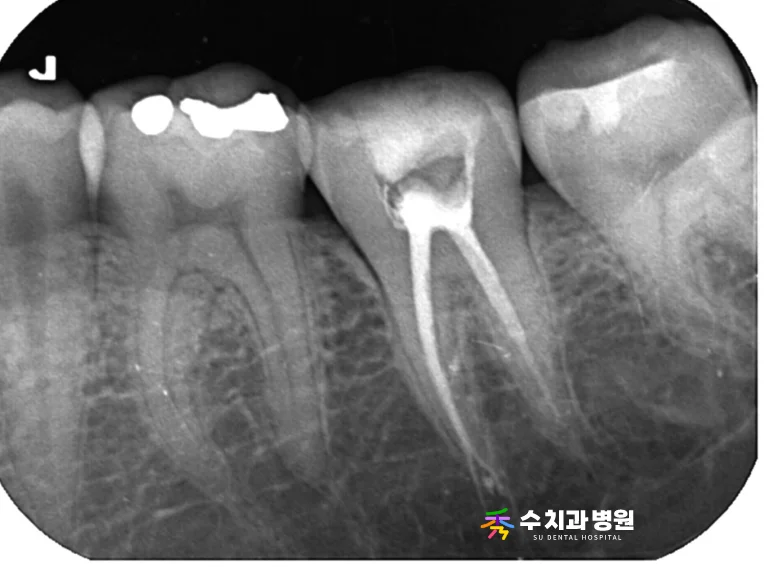

[📸 치료 전 엑스레이사진] (촬영일: 2024년 10월)

방사선 사진과 임상 검사를 꼼꼼히 진행한 결과,

과거 깊은 충치로 치료했던 기존 레진 부위가

치아 내부의 신경과 매우 가까운 상태였습니다.

이로 인해 음식을 씹을 때마다 신경에 자극이 가해져,

통증이 유발된 것으로 진단되었습니다.